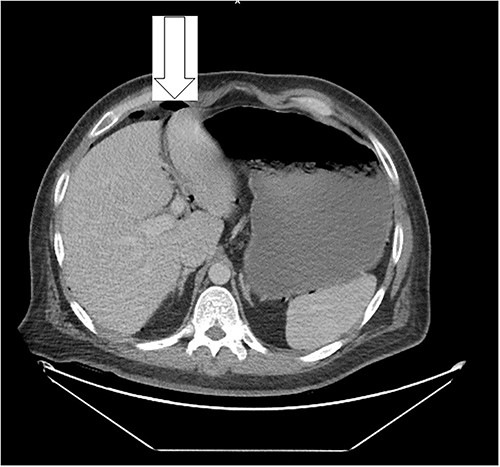

Eleven days post-discharge, he presented to the ER with the same symptoms. CT once again demonstrated pneumoperitoneum (see Fig. 3). Perforated hollow viscus structure is suspected; however, no rim-enhancing abscess is evident. Given his previous two negative ex-laps, a repeat EL was deferred. A conservative treatment plan of pneumoperitoneum was implemented for IP.

Amount of pneumoperitoneum increased compared with previous CTs.